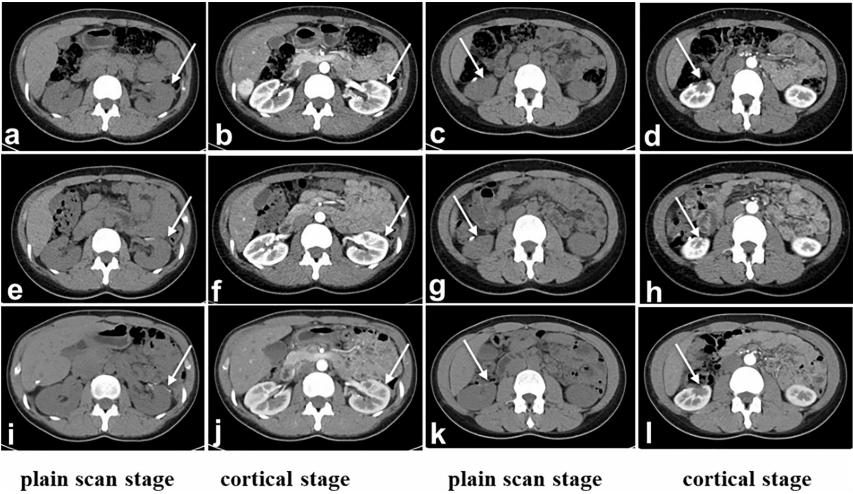

术后,患者每天注射干扰素9×106 IU,持续3个月,每两周注射尼沃单抗OPDIVD 100 mg/次,持续12个月,作为预防肿瘤复发的预防性治疗,未出现副作用。术后1年CT未发现肿瘤复发或转移时,免疫治疗结束。治疗期间和治疗后,红细胞和白细胞计数以及肾功能指数均在正常范围内。第二次手术后第三、第六和第24个月进行CT检查(图3)。患者在第二次手术后28个月怀孕,第二次术后38个月生下孩子。怀孕期间,患者没有肾癌的临床表现;到目前为止,没有出现肿瘤进展。

图3. 术后CT检查。(A-D):术后第三个月,(E-H):术后六个月。左上肾(A、B、E、F、I、J)和右下肾(C、D、G、H、K、L)的边缘不规则。双侧肾脏的肾周间隙清晰,形状和大小正常。腹膜后未见明显肿大淋巴结影。